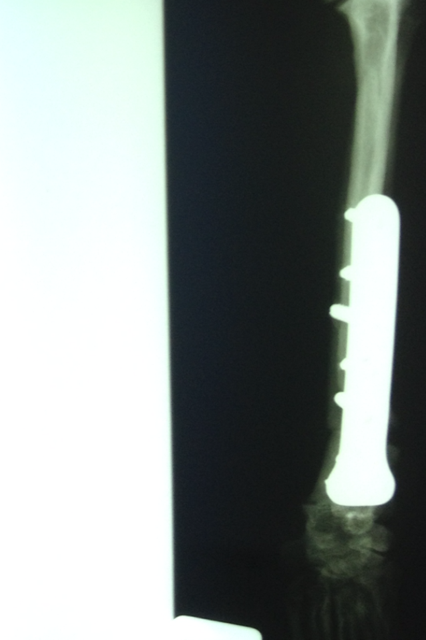

Wir waren alle sehr aufgeregt. Und selbst der erfahrene Arzt meinte, es sei eine ungewöhnliche Aktion, denn normalerweise weist nur ein Pfötchen so starke Anomalien auf. Er hatte es noch nicht, dass beide operiert werden müssen.

Wir danken herzlich für die Geldspenden, die dies alles erst ermöglicht haben - aber bitten auch dringend um weitere Überweisungen, denn wir mussten heute auch Griffin operieren lassen, der sich mit Kniescheibenproblemen herumplagte. Und weil Lucy auch Probleme zu haben scheint, haben wir sie heute mitgenommen zum Röntgen. Es stellte sich leider heraus, dass sie einen Kreuzbandriss hat, der ebenfalls operiert werden muss.